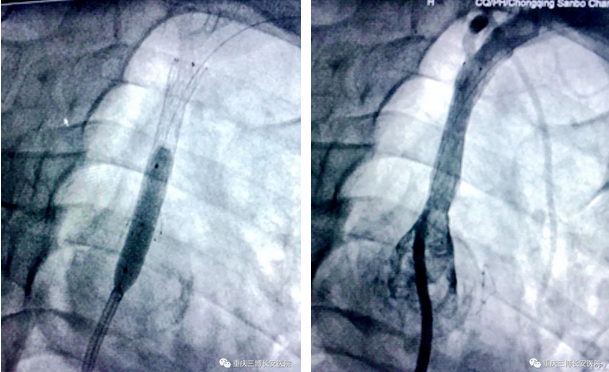

经三博长安医院神经内科团队集体讨论,介入团队在DSA室为刘先生行了左锁骨下动脉球囊扩张术、支架植入术,右侧椎动脉支架植入术,DSA显示左侧椎动脉血流立即调头流向大脑,右侧椎动脉血也恢复正常。

经过介入治疗,刘先生说话从此流利不打结,不晕厥,右侧肢体力量有很大改善,虽然左侧肢体力量还差一点,但已经走路无忧,活动自如。仅仅住院11天,一年多来缠绕他和家人的怪病彻底消除,刘先生康复出院。